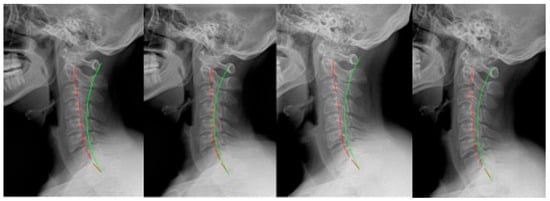

2. Materials and Methods

3. Results

| Post- MVC (Pre-2nd rehab) | ARA | −17.7° | +9.1° | −20.3° | −18.1° | −15.4° | −17.3° | −22.2° | −14.6° (10.7°) |

| TzH | 18.7 mm | 26.6 mm | 11.3 mm | 12.8 mm | 36.4 mm | 21.2 mm | 20.9 mm | 21.1 mm (8.5 mm) | |

| APL | −10.6° | −7.4° | −23.3° | −14.8° | −12.8° | −25.5° | −18.7° | −16.2° (6.7°) | |

| Post- MVC rehab | ARA | −30.0° | −14.0° | −37.8° | −28.6° | −35.1° | −32.7° | −30.0° | −29.7° (7.7°) |

| TzH | 11.7 mm | 10.3 mm | −3.7 mm | 15.5 mm | 11.8 mm | 13.9 mm | 11.6 mm | 10.2 mm (6.3 mm) | |

| APL | −20.1° | −21.9° | −36.1° | −19.1° | −23.9° | −35.0° | −29.8° | −26.6° (7.1°) | |